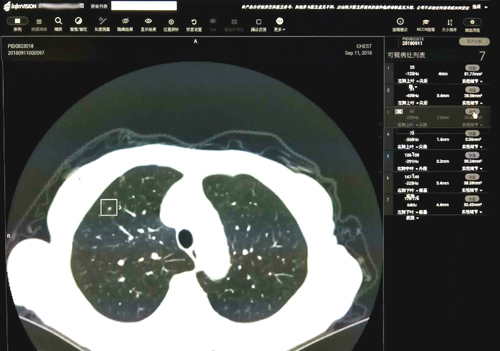

这款由推想科技提供的软件结合临床医学院/附属医院最先进的 256排512层高端螺旋CT扫描的肺部图像,以其高性能的并行运算能力,通过测量CT值识别出实性、磨玻璃及钙化结节并同时显示所有结节的大小、体积。有了该软件的辅助,再小的结节也不易漏诊。影像科医生对检测的结节进行分析,反馈至软件中标记假阴性的结节和取消假阳性结节的标记。此外,它可通过对影像组学的自我深度学习,提高对图像全信息识别利用的诊断准确性;并且它的知识经验会随着病例增多不断自我优化,从而不断降低漏诊率、误诊率。